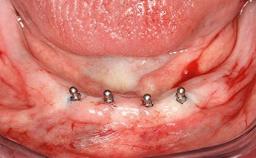

Improving an Existing Implant-supported Denture in an Alzheimer Patient with Bipolar Affective Disorder with Moderate Depression and Dementia

An 83-year-old man presented together with his caregiver at the dental department of the Medical University of Innsbruck, Austria with complaints of swelling in the right maxillary canine area and loss of retention of his 5-years-old mandibular denture. The patient had a significant medical history (20 years) of bipolar affective disorder with moderate depression (F 31.3) and dementia in Alzheimer’s disease (F 00.2). The patient had been in ambulant psychiatric therapy for his depressive illness for the past 20 years. He lived alone and had no children; his sister assisted with daily living. She reported that the patient exhibited compulsive hoarding behavior. In the previous two months, she had noted increasing disorientation and vertigo in the patient. She therefore accompanied him for a medical consultation at the Department of Psychiatry and Psychotherapy of the Medical University of Innsbruck. He was released home after a 6-week inpatient stay.

Case Type Edentulous Mandible

Jaw Mandible

Area Full-Arch

# of Implants 2

Defining Characteristics Fully edentulous lower jaw to be rehabilitated with two or more implants

Modality 2 interforaminal implants